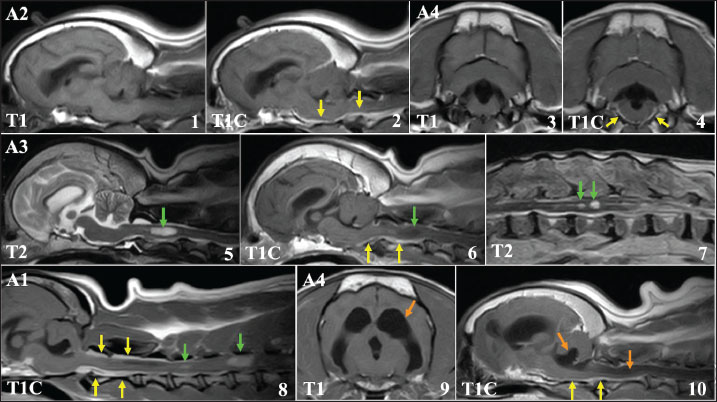

However, in 4 cases, the neurological signs recurred after a period of clinical stability, and the owners of these cases requested MRI re-evaluation when clinical symptoms recurred (cases A1–A4). The median duration between the end of radiotherapy and clinical worsening was 256 (range: 28-457) days. At the time of recurrence, all 4 cases exhibited ataxia, and 1 case could not stand unaided. In addition, epileptic seizures recurred in 2 of the 4 cases despite antiepileptic medical treatment. The MRI features of these cases are described in detail below. These cases then worsened, with death eventually resulting from the progression of neurological symptoms.

Magnetic resonance imaging of recurrent cases (A1–A4)

The MRI features of these recurring cases (A1–A4) are shown in Fig. 4. In all 4 cases, MRI showed that the primary tumor tissues had almost completely disappeared. However, in the contrast study, sagittal T1-weighted images of these 4 cases showed clear enhancement in the leptomeningeal region, which was most evident in the area spanning the ventral side of the brainstem to the cervical spinal cord (Fig.4,1-4). In addition to these leptomeningeal enhancements, two cases (A1 and A3) had space-occupying lesions in the cervical and/or thoracolumbar spinal cord along the central canal of the spinal cord (Fig.4,5-8). The signal intensities of both lesions were slightly low in T1-weighted images, and slightly high in T1-weighted and T2-weighted images, respectively. The spinal lesion showed only minor enhancement in one patient, but there was clear enhancement in the other. Furthermore, in case A3, multiple mass lesions were found in the thoracolumbar spinal cord (Figs. 4 and 7). Significant obstructive hydrocephalus was observed in one case (A4, Fig.4, 9-10). These findings are highly similar to those showing CSF drop metastasis, which was recently reported in dogs (Vigeral et al., 2018; Bentley et al., 2021).

Fig. 4. MRI findings of FB cases in which clinical symptoms recurred after radiotherapy (cases A1–A4, T1: T1-weighted image, T2: T2-weighted image, T1C: T1-weighted image with contrast medium). Upper lane (1–4): A clear enhancement was observed in the meninges around the brainstem (yellow arrows). Middle lane (5–7): Spinal lesions observed at clinical recurrence (green arrows). The lesion located in the central cervical spinal cord of case A3 showing high-signal intensity on T2-weighted image (5) showed no contrast enhancement (6, green arrow), whereas the leptomeningeal region showed clear enhancement (6, yellow arrows). Multiple lesions were also observed in the thoracolumbar spinal cord in this case (7). Lower lane (8–10): Cervical spinal lesions in patient A1. Unlike case A3, these lesions showed clear enhancement, similar to that of the leptomeningeal region (8, green arrows). In case A4, severe obstructive hydrocephalus was observed, with dilated lateral (9) and fourth (10) ventricles (orange arrows).

To investigate the causes of the shorter MST, we re-examined the MR images obtained at the recurrent phase in four cases (A1–A4). Contrast enhancement of the leptomeninges around the brainstem was observed in all 4 cases. In a report by Vigeral et al. (2018), similar MRI findings of ventral brainstem leptomeningeal enhancement were obtained after radiotherapy for oligodendroglioma in the English bulldog, and the investigators interpreted these data as indicative of CSF drop metastasis, using this term for the first time in small animal practice. CSF drop metastasis refers to tumor metastatic forms in which metastatic lesions are formed within the brain, and in some cases, within and/or around the spinal cord by tumor cells disseminated into the CSF. Nakamoto et al. (2018) reported similar MRI findings, suggestive of CSF drop metastasis, during follow-up of an oligodendroglioma in a single case of FB treated with radiotherapy. In the report, acceptable local control of the primary lesion was obtained before clinical symptom recurrence, as in our cases. In addition to leptomeningeal enhancement around the brainstem, lesions in the spinal cord and an obstructive hydrocephalus were concurrently observed at the recurrent phase in 2 cases and in one case, respectively. These MRI features have also been described in previous reports; in their cases, Vigeral et al. (2018) and Nakamoto et al. (2018) reported lesions in the spinal cord and significant hydrocephalus, respectively. The MRI findings in the present study were consistent with previously reported characteristics of CSF drop metastasis.